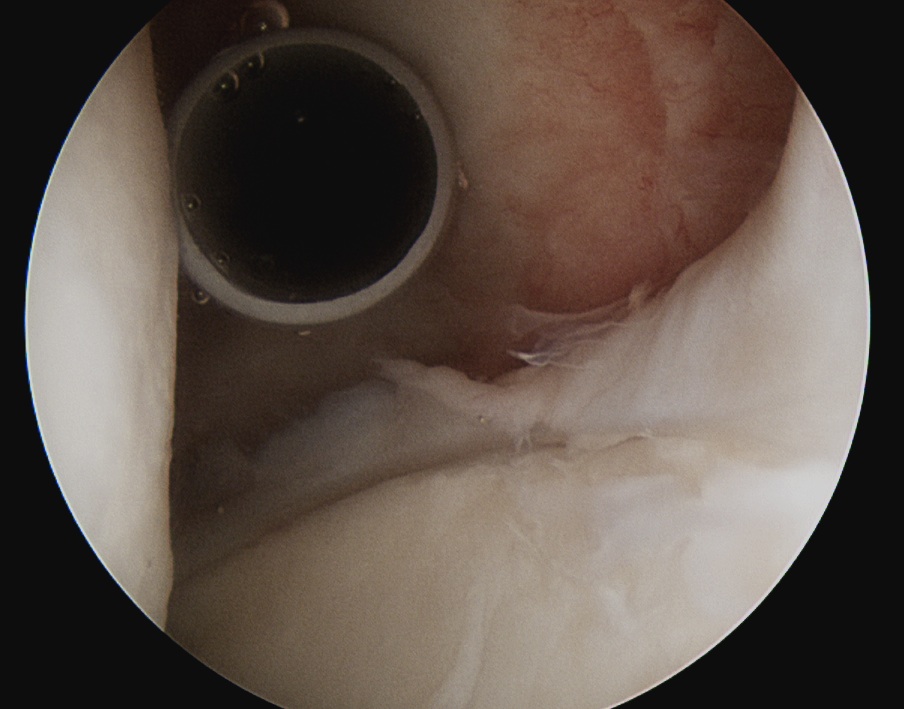

Posterior labral repair

Posterior capsular plication